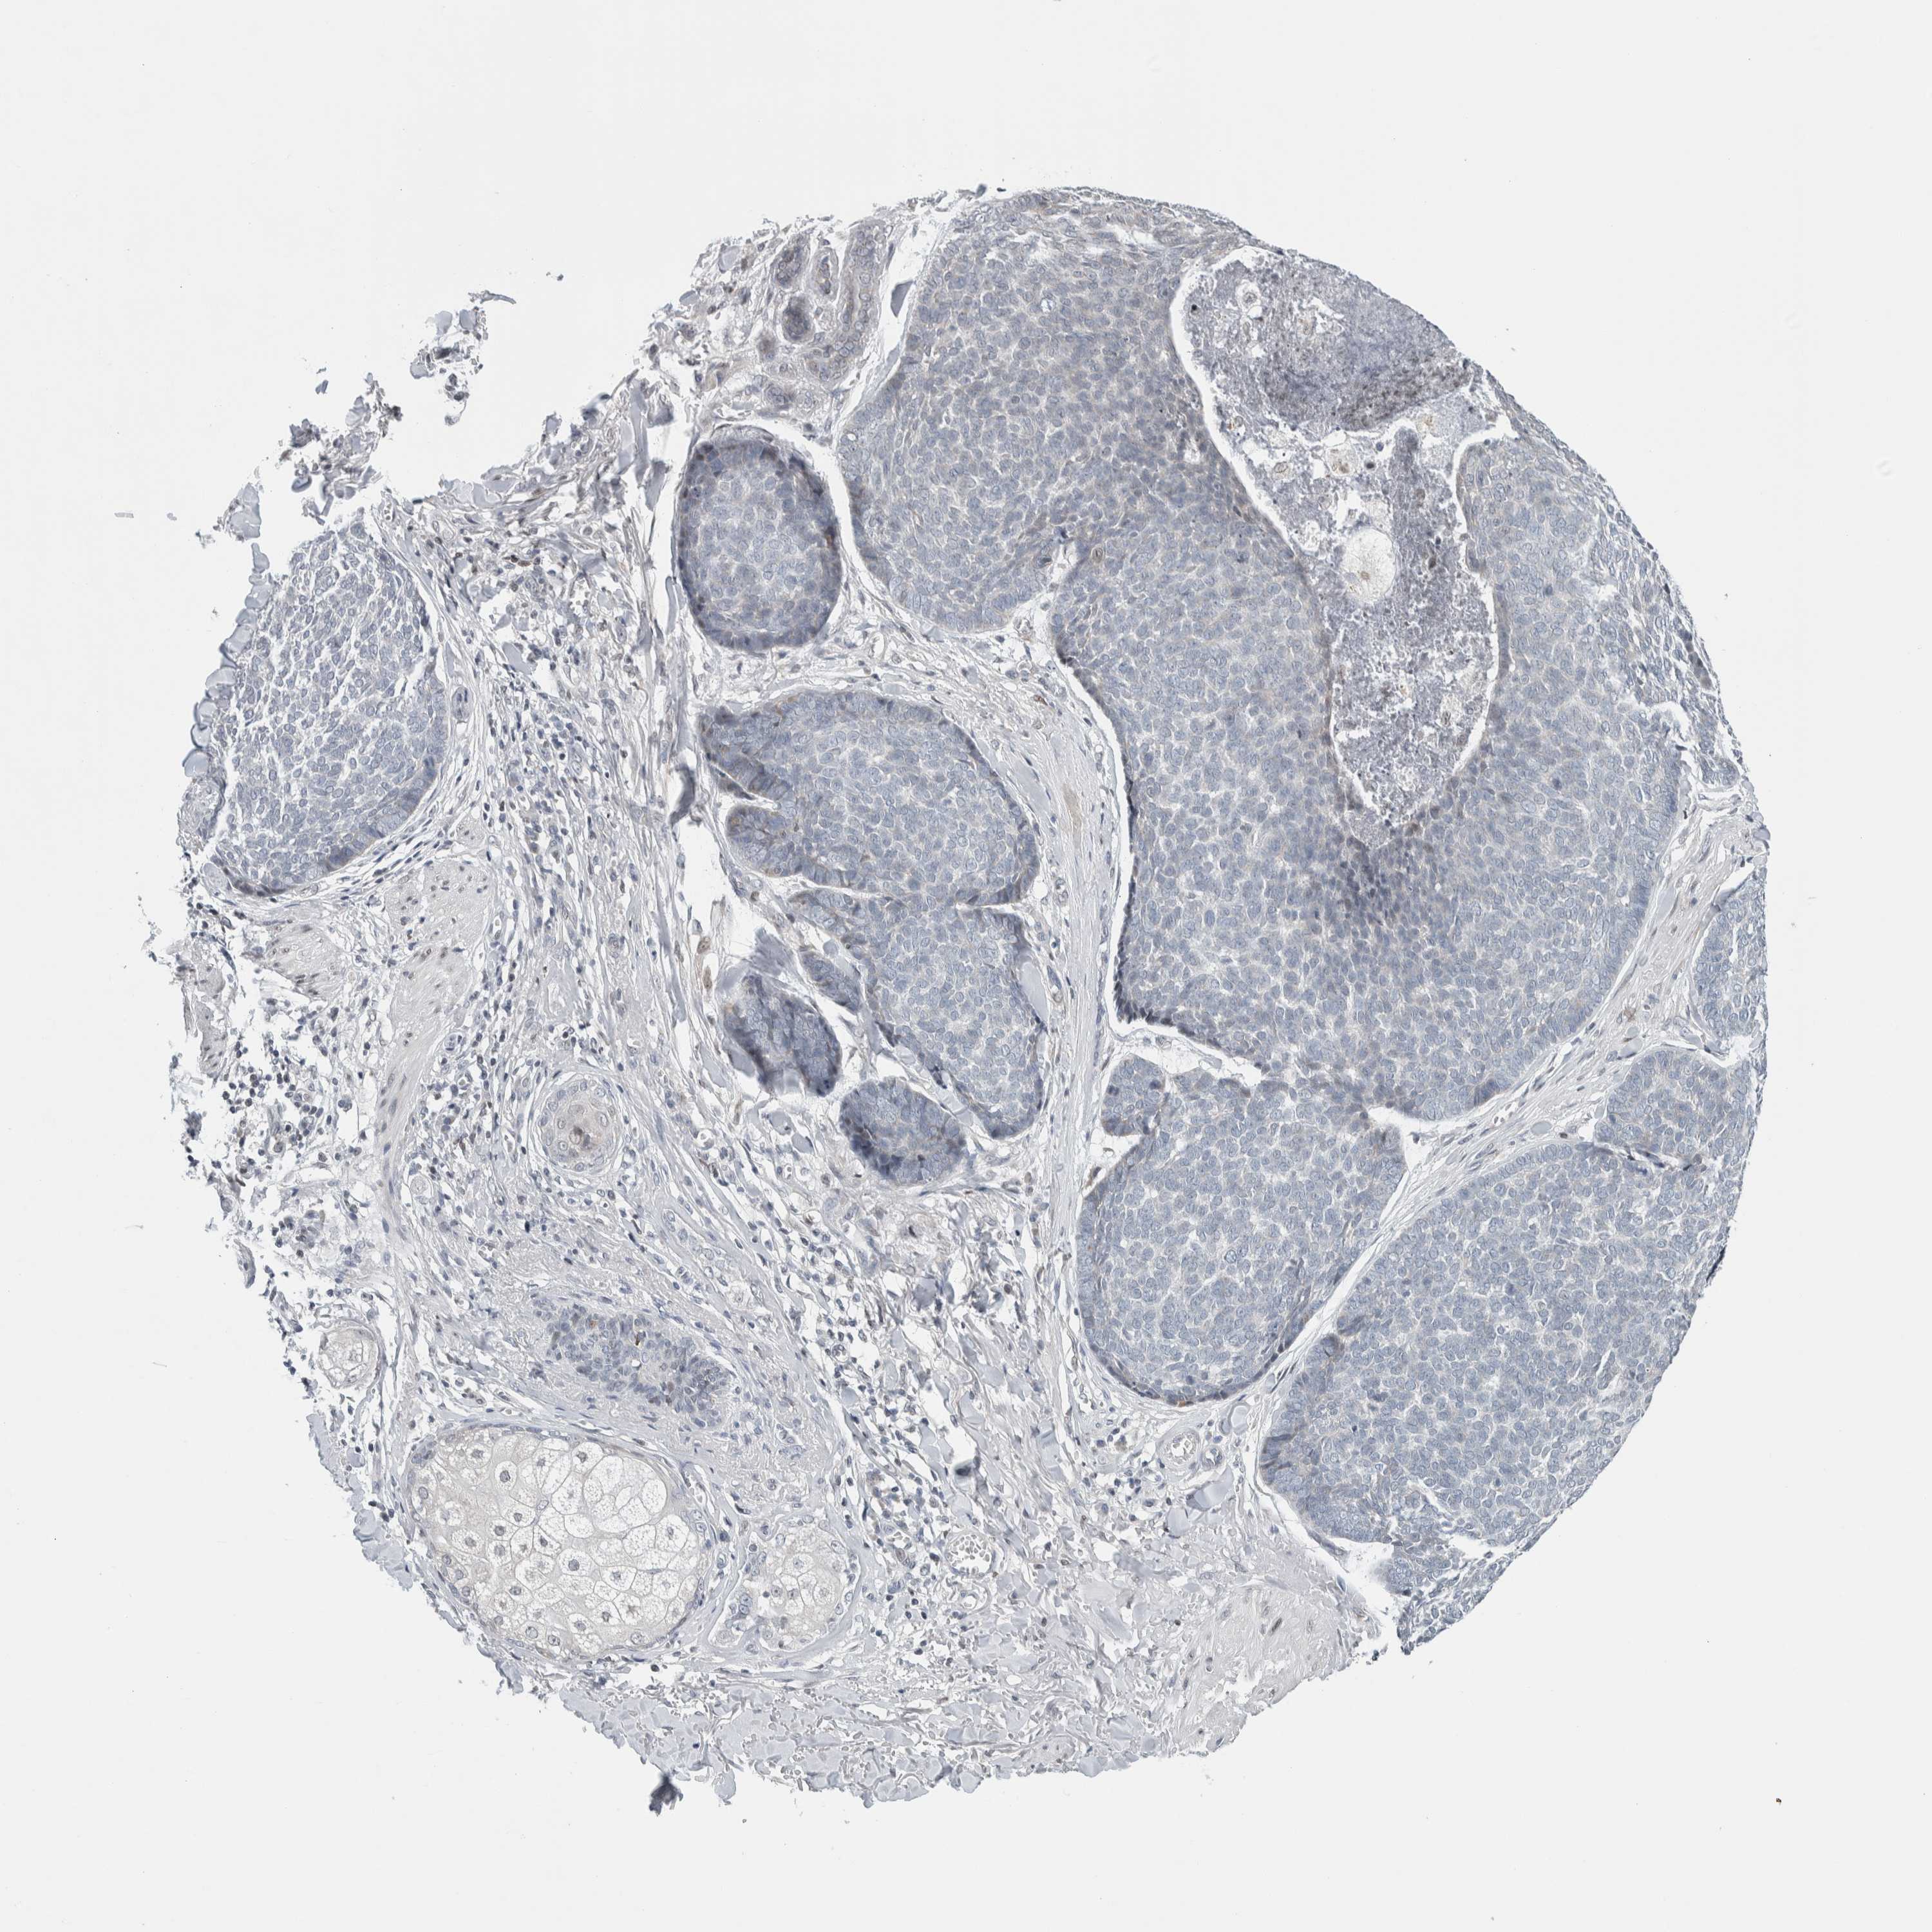

SKIN CANCER - Protein expressioni

A mouse-over function shows sample information and annotation data. Click on an image to view it in a full screen mode. Samples can be filtered based on level of antibody staining by selecting one or several of the following categories: high, medium, low and not detected. The assay and annotation is described here.

Antibody stainingi

Antibody staining in the annotated cell types in the current human tissue is reported as not detected, low, medium, or high, based on conventional immunohistochemistry profiling in selected tissues. This score is based on the combination of the staining intensity and fraction of stained cells.

Each image is clickable and will lead to virtual microscopy that enables deeper exploration of all samples and also displays staining intensity scores, fraction scores and subcellular localization as well as patient and tissue information for each sample.

Antibody HPA003278

Antibody CAB022450

Squamous cell carcinoma, NOS

Basal cell carcinoma